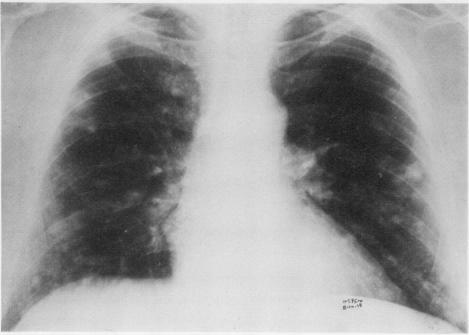

A case of multiple nodular pulmonary amyloidosis in a 54-year-old Caucasian man is presented. Discrete symptomless radiodensities had developed in this patient's lungs within a period of three years, leading to a suspicion of a neoplastic process. The amyloid nature of these nodules was demonstrated by biopsy. In this case, as in others previously reported, there was no evidence of systemic disease, and immunoglobulins were normal. Local factors probably play an important part in the pathogenesis of this disease. This entity is to be distinguished from the diffuse type of pulmonary amyloidosis, which has a far graver prognosis. Diffuse alveolar septal amyloidosis is usually associated with primary systemic amyloidosis or multiple myeloma and leads rapidly to respiratory distress.